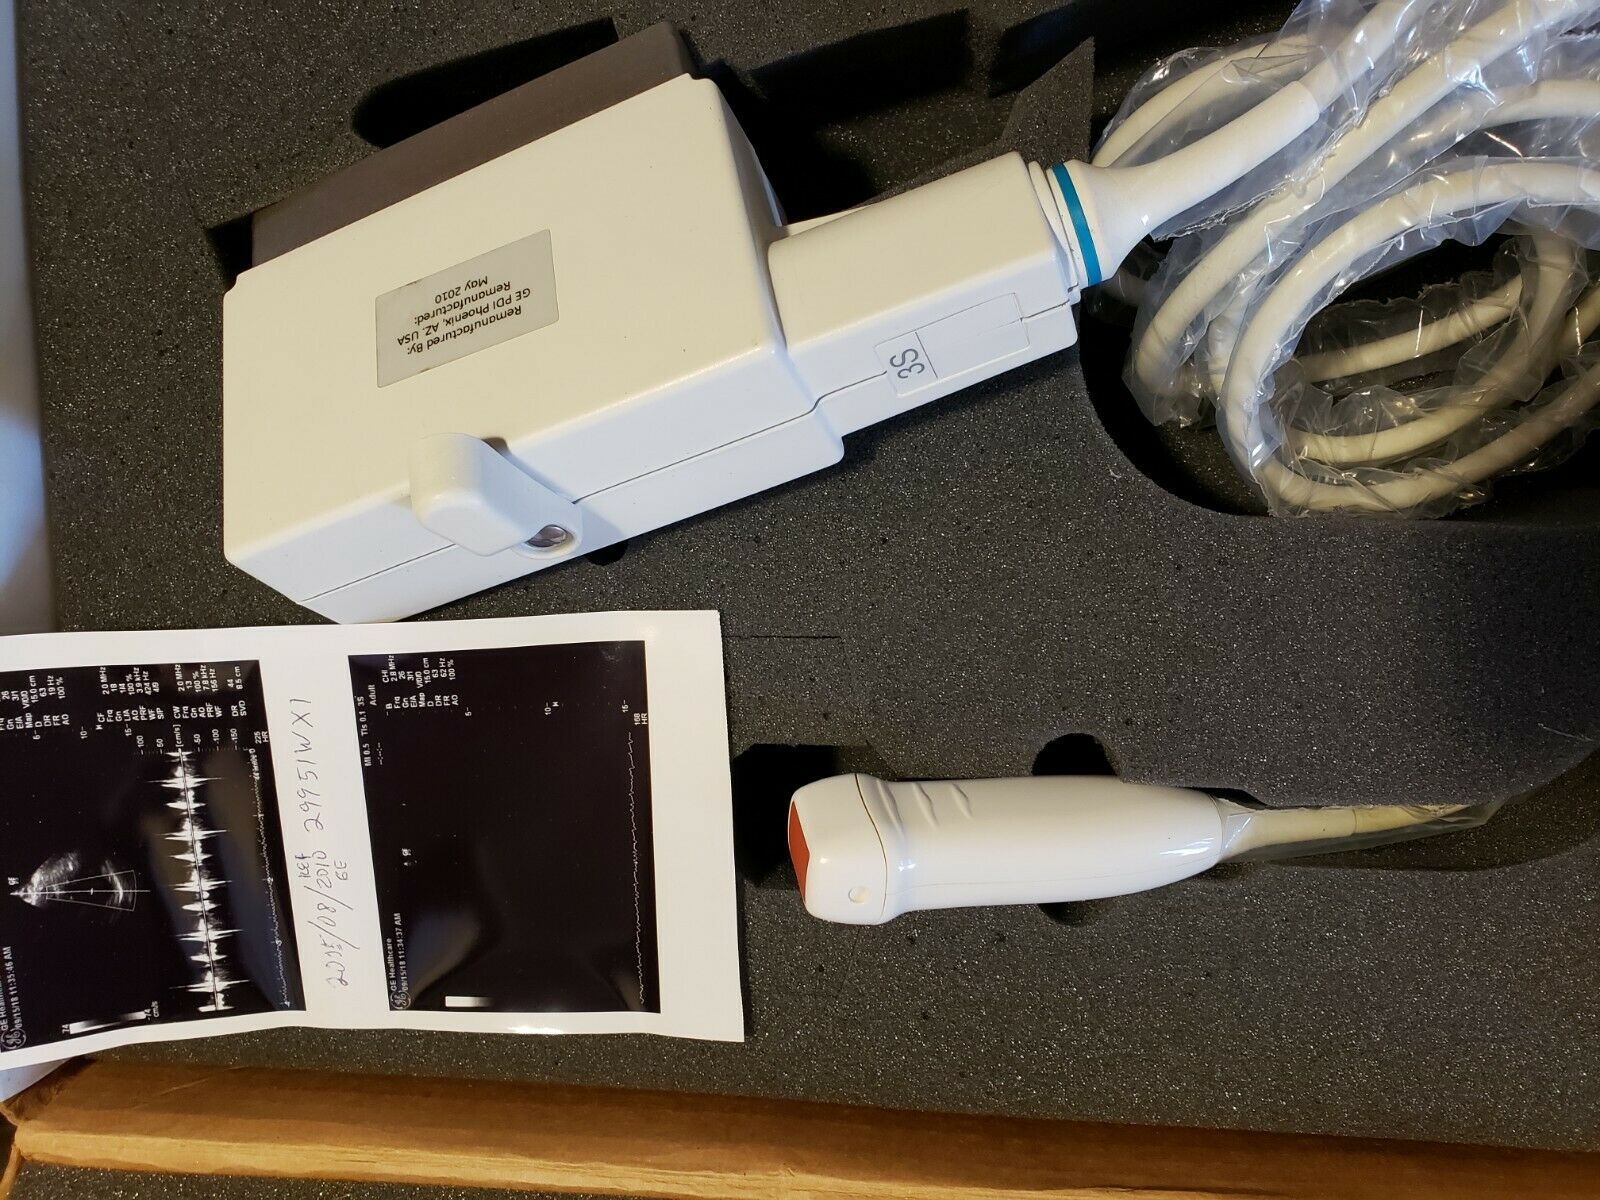

DIAGNOSTIC ULTRASOUND MACHINES FOR SALE

GE 348c Ultrasound convex ultrasound transducer

Sale price$ 1,439.90